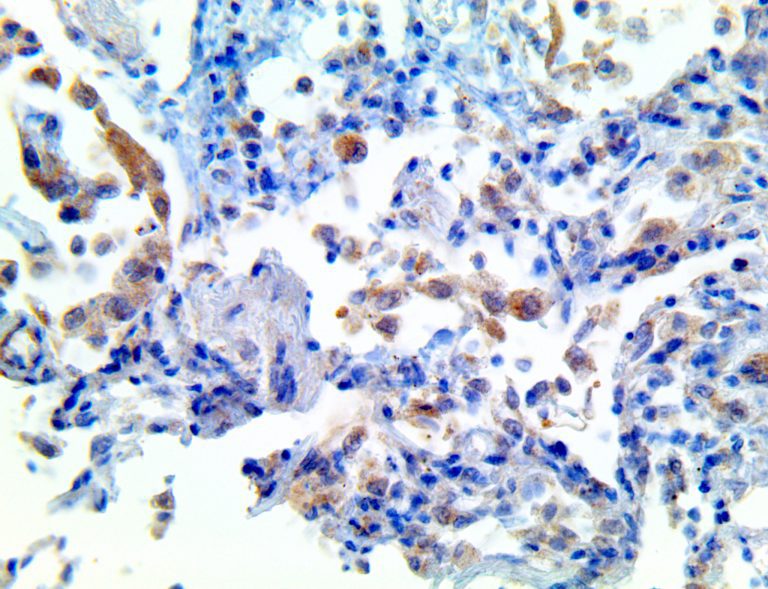

The first cytokines released are interleukin 1β (IL-1β) and tumor necrosis factor-α (TNF-α), which attract a variety of circulating white blood cells (WBCs) to the infection site, including neutrophils, monocytes, macrophages, and natural killer (NK) cells. This response, along with the antipathogenic chemicals released by these cells (i.e., complement), comprise the innate immune response. These cells directly attack the invading pathogen and also release additional cytokines, chief among them interleukin-1 and 6 (IL-6). IL-6 is essential for invoking the adaptive immune response, which calls T-cells, B-cells, and T helper (Th) cells to the infection site. IL-6 also stimulates further recruitment, proliferation and activation of macrophages.

It is the ICU physician who is most likely to witness one of the deadliest manifestations of the abnormal immunological response, the cytokine storm syndrome (CSS). This response is also referred to by some as the cytokine release syndrome (CRS). CSS is characterized by continuous activation and expansion of macrophage and lymphocyte populations, which secrete large amounts of cytokines, causing the cytokine storm. This massive cytokine release is akin to hemophagocytic lymphohistiocytosis (HLH) disease, a syndrome characterized by initial unchecked and persistent activation of cytotoxic T lymphocytes and NK cells.

This activation induces inflammatory monocytes to highly express IL-6, starting a localized and then systemic cascade effect that results in hyperproduction of IL-6, which accelerates the inflammatory process. Because IL-6 also increases vascular permeability, excessive levels cause blood vessels to become very leaky. This, along with clotting factors released from vascular endothelial cells, stimulates the coagulation cascade, resulting in microthrombosis (tiny clots), which leads to ischemia and tissue death of the kidney, intestines, heart, liver, brain and extremities.